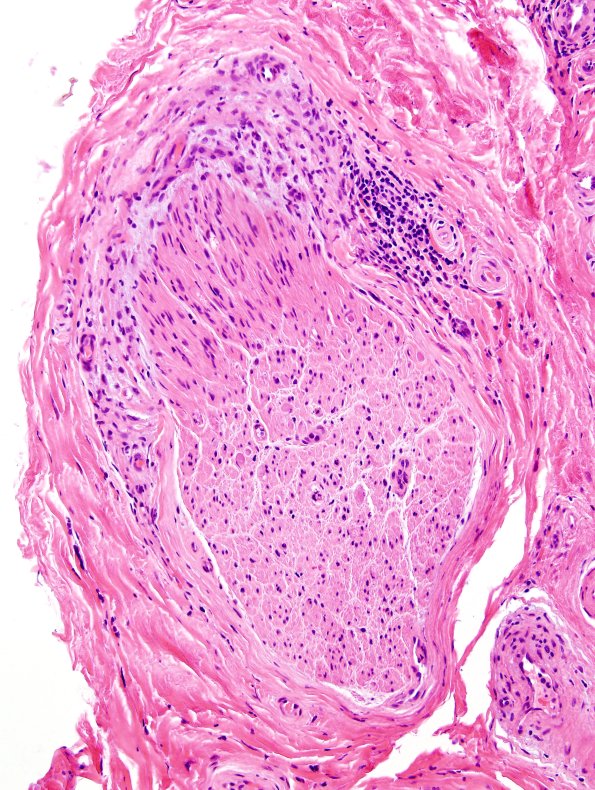

Washington University Experience | PERIPHERAL NEUROPATHY | 7A GUILLAIN-BARRE SYNDROME (GBS) | 2A3 GBS (Case 2) H&E 2

2A3 GBS (Case 2) H&E 2

Higher magnification of image #2A1. (H&E)